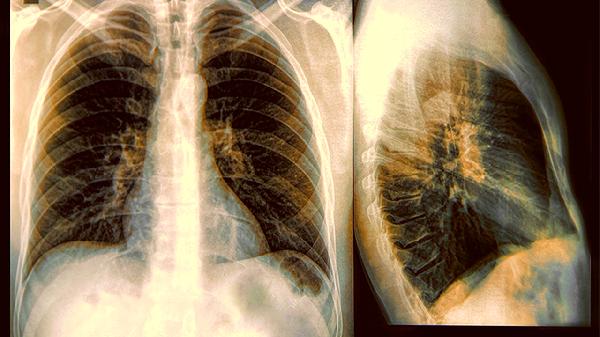

1、密度变化预警

当纯磨玻璃结节开始出现实性成分,就像透明果冻里混进了硬糖粒,这个叫做"实性占比"的指标是重要的观察窗口。不过从出现实性成分到具备威胁性,往往还需要跨越好几个复查周期。

2、血管生成信号

结节周围如果出现新生的血管网络,相当于给潜在问题安装了营养输送管道。但这个变化需要通过特定检查才能发现,普通CT就像隔着毛玻璃看风景,这也是为什么医生有时会建议升级检查手段。